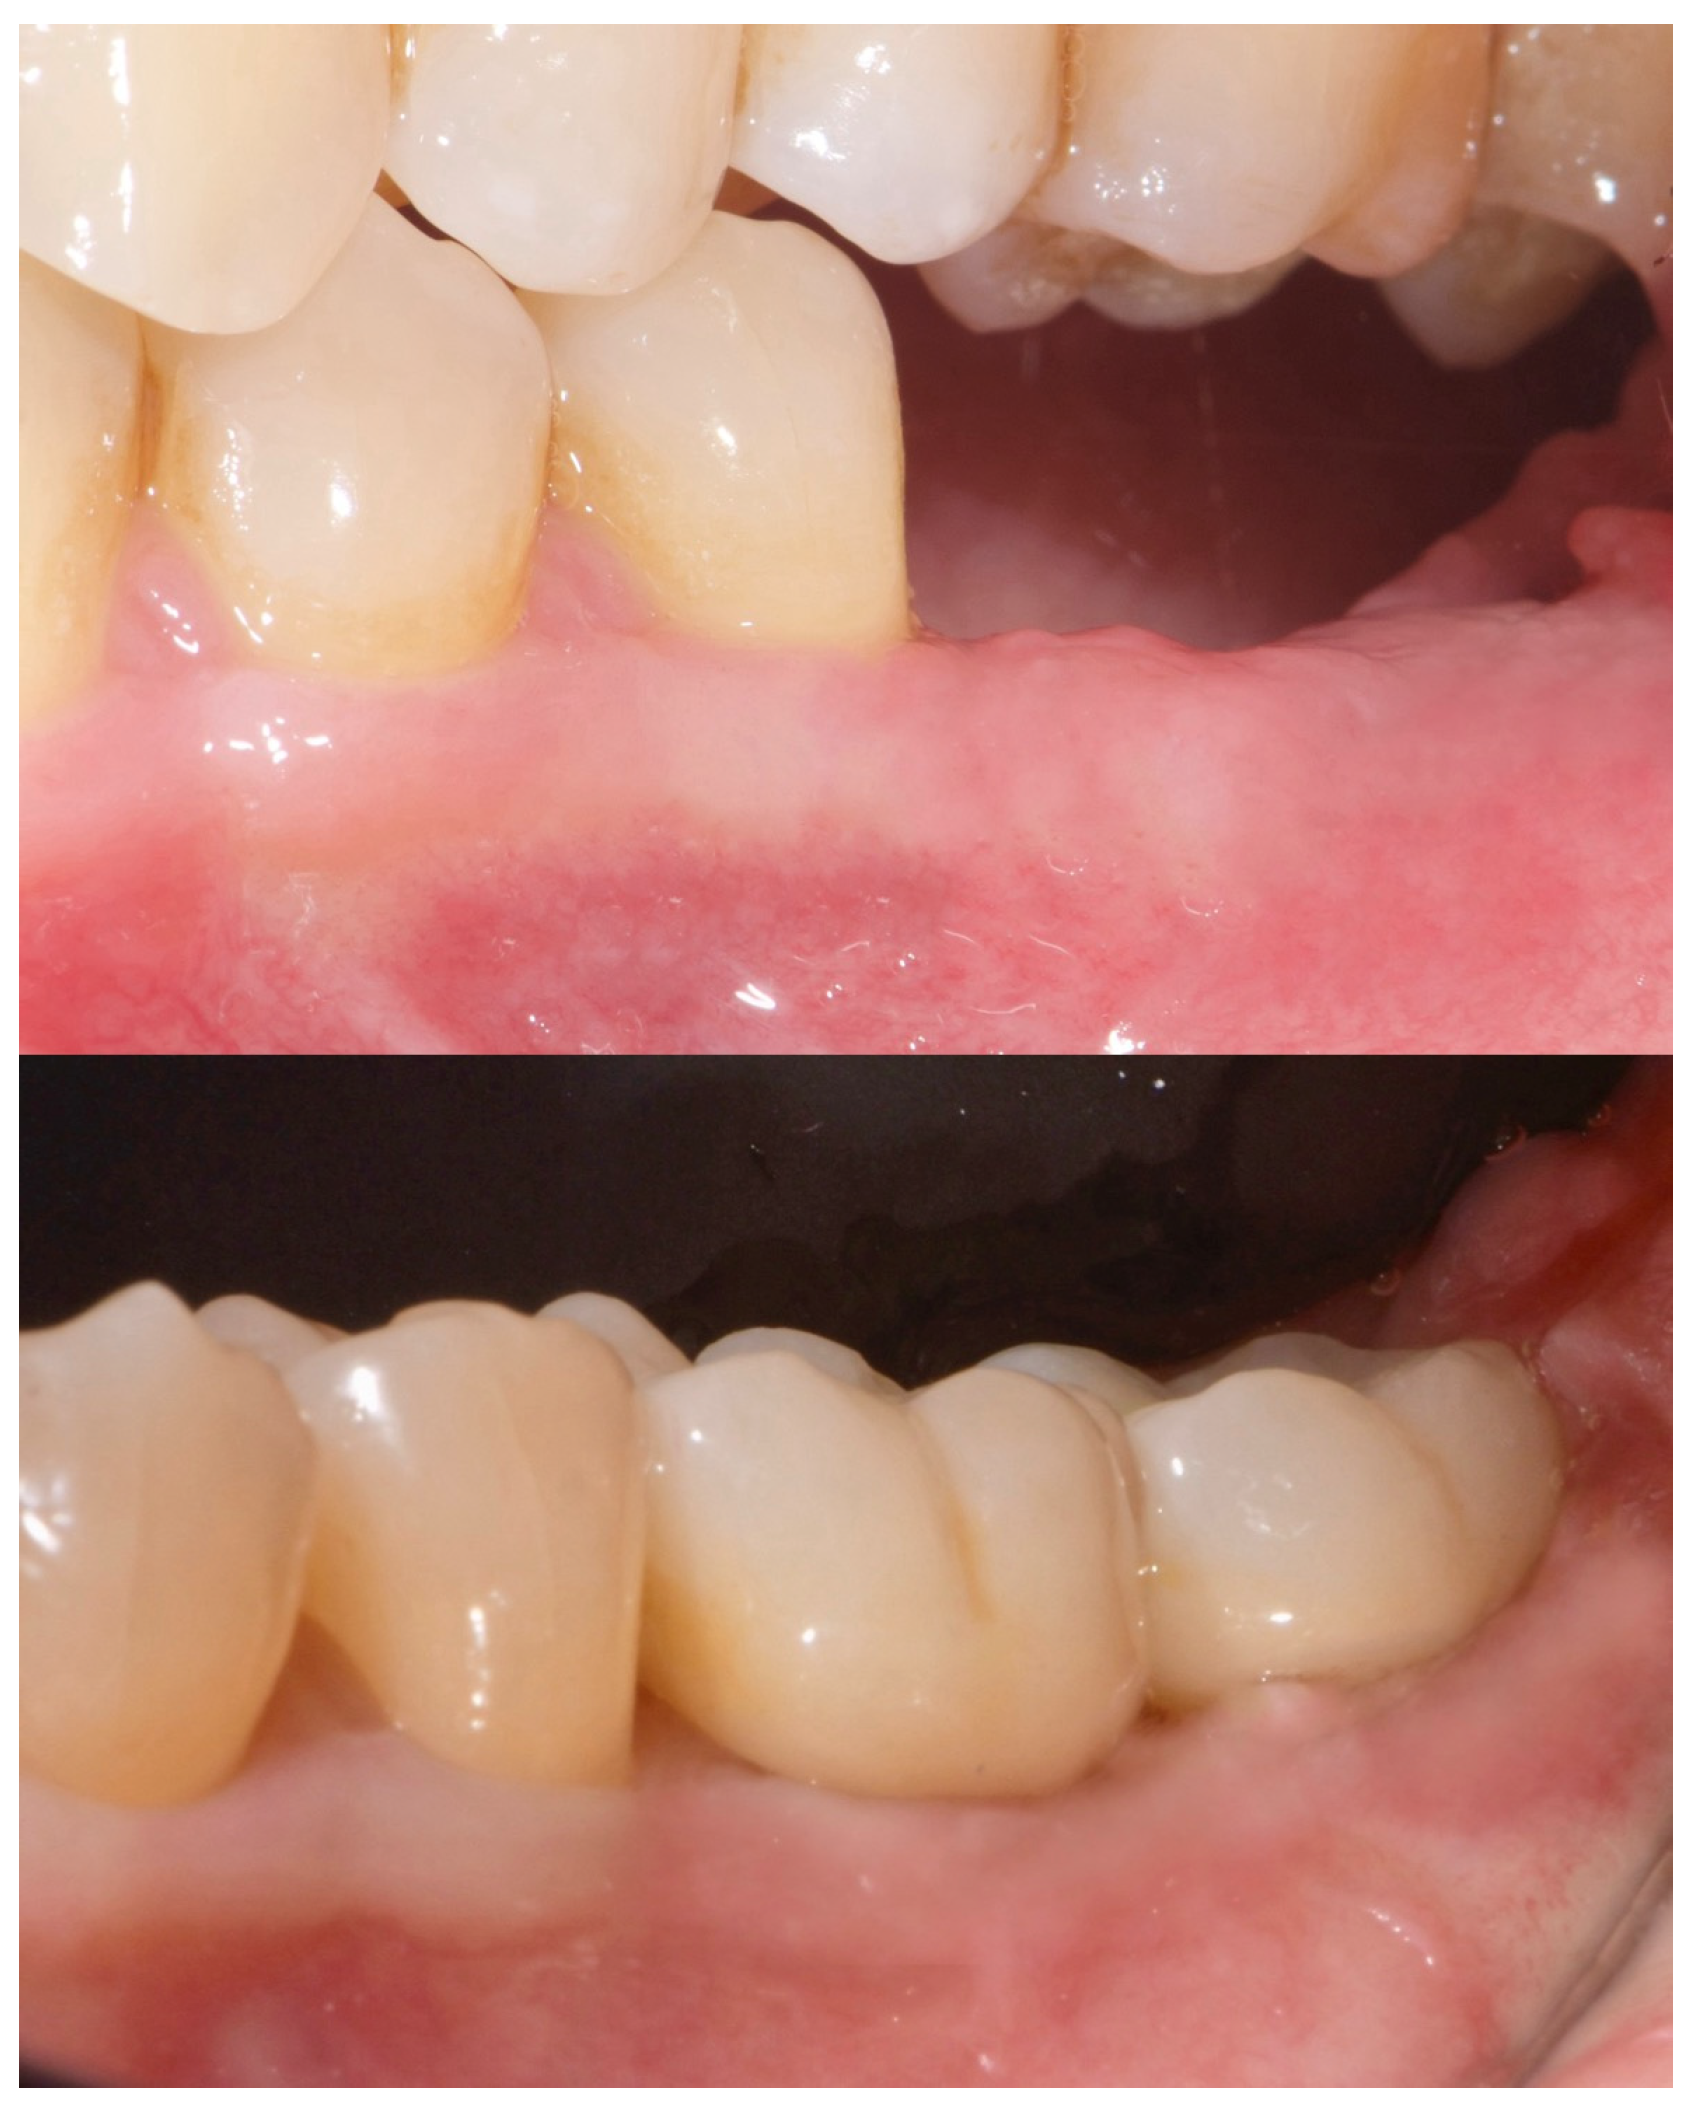

2. Case Summary